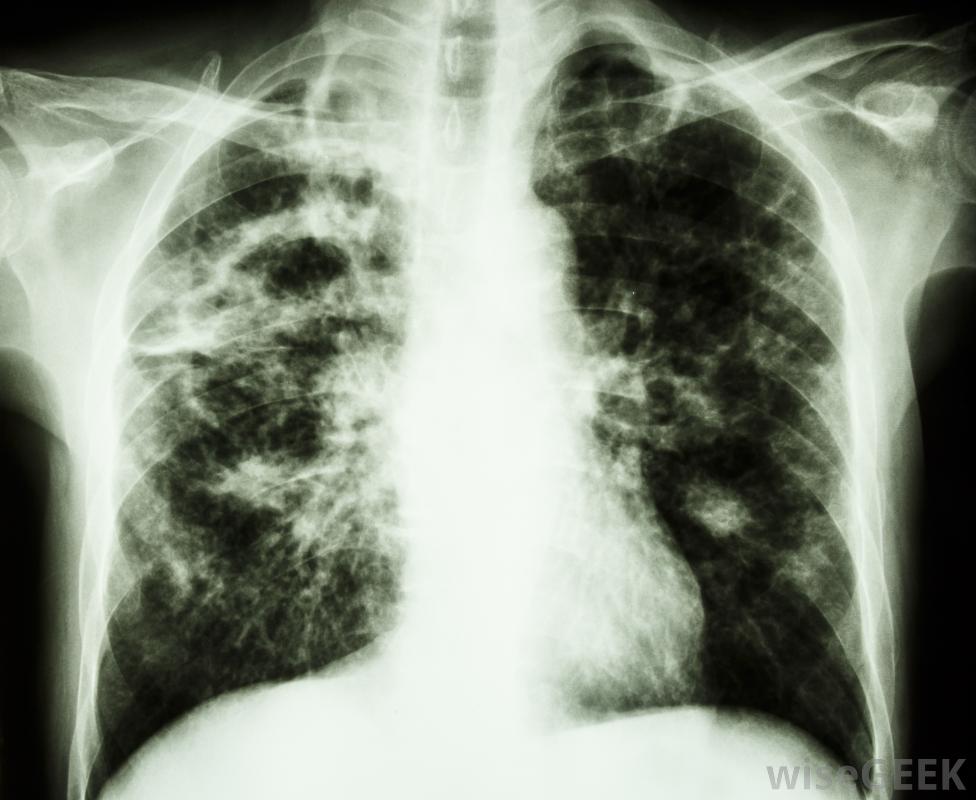

引起结核病感染的细菌常用于弗氏完全佐剂中佐剂是一个通用术语,指用于产生抗体的试剂。为了产生抗体,一种实验室哺乳动物,如小鼠或兔子接受免疫。免疫溶液含有抗原和佐剂。这些抗原诱导称为囊源性(B)细胞的免疫细胞增殖并产生免疫球蛋白或抗体,这些免疫球蛋白或抗体专门针对抗原。通过这个过程产生的抗体是多克隆的,这意味着它们来自不同的B细胞。